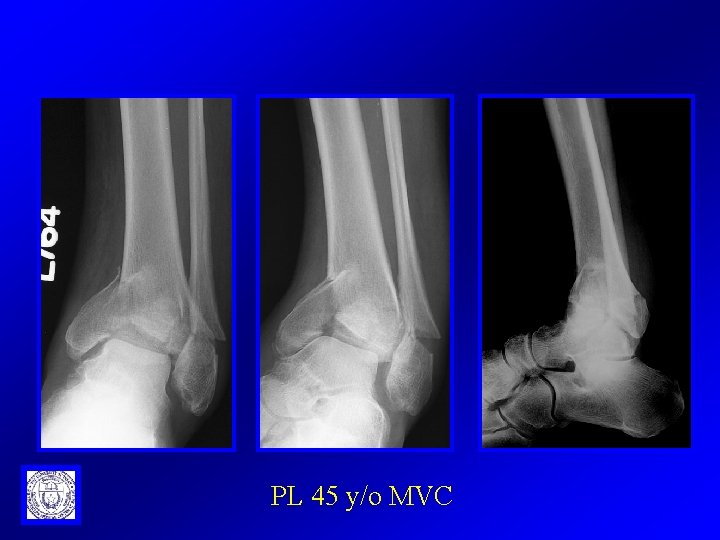

PL 45 y/o MVC